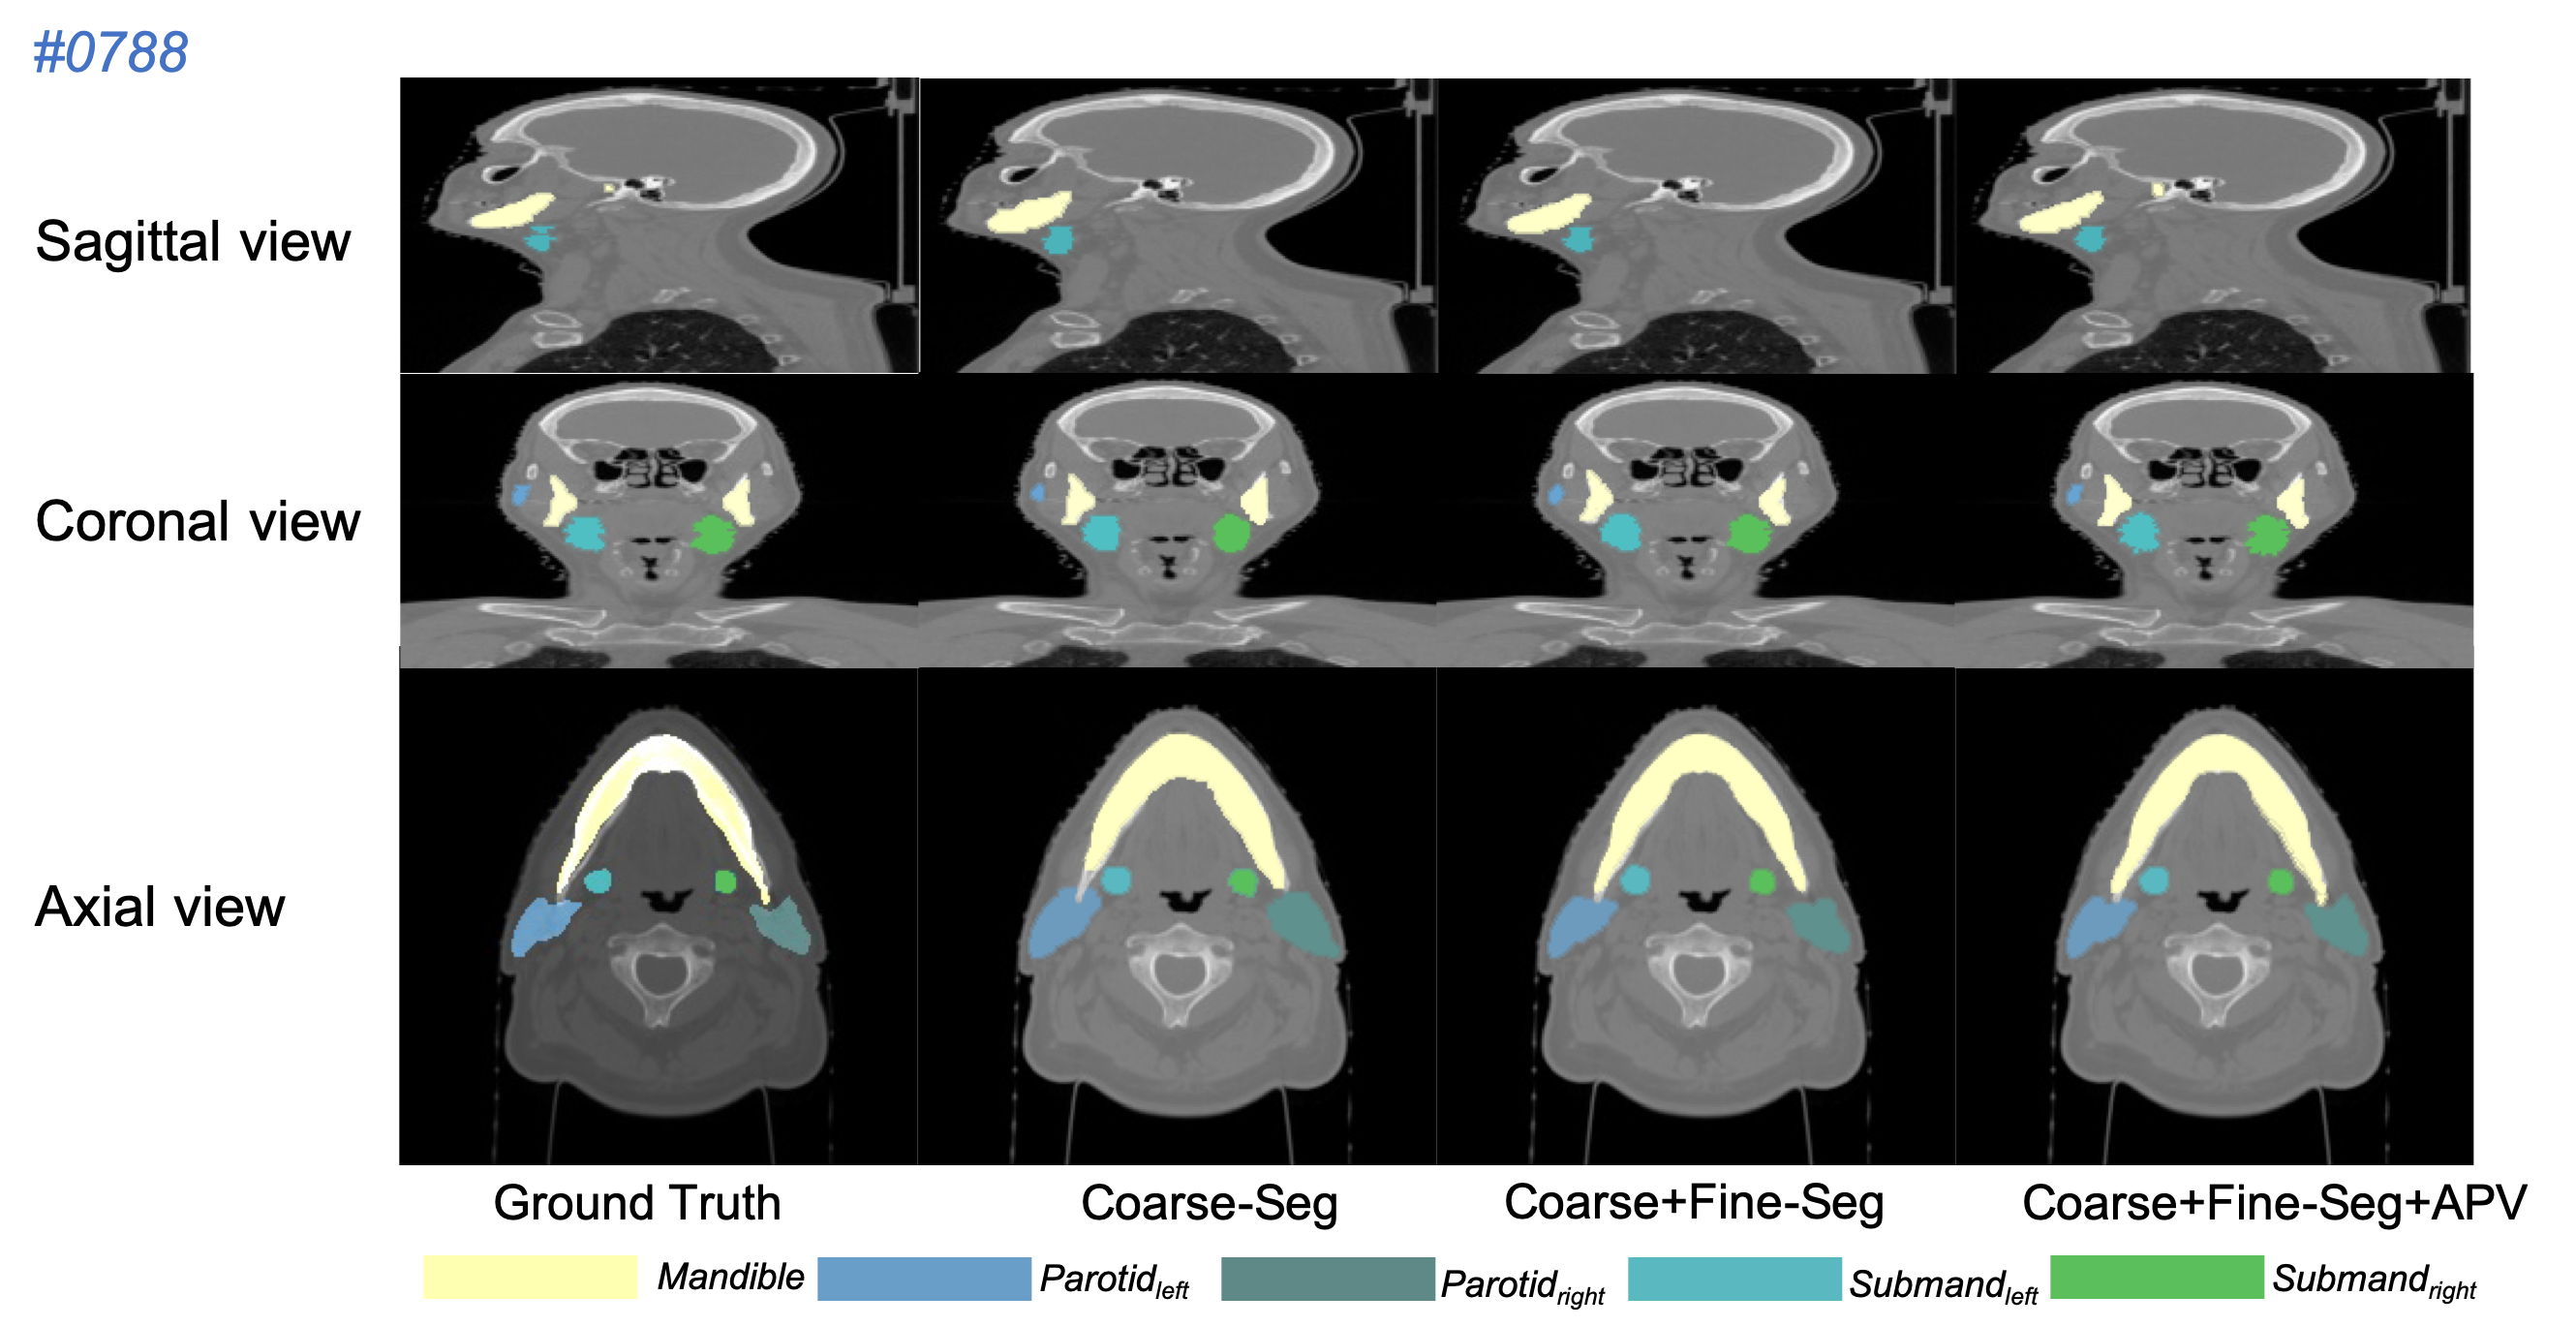

Refer to caption

Figure 6: Example results of multi-organ segmentation on the instituted head-and-neck dataset.

Tab. 3 illustrates an ablation study on the instituted H&N dataset, where the accuracy (average DSC(%)) of coarse-scale, fine-scale and APV refined segmentation are reported. Compared with [40] that processes on 2D images in fine-scaled segmentation, our method has made a improvement (12%1percent21~{}2\% DSC) in the fine-scaled segmentation since it performs directly on 3D volume for all reported OARs, including some challenging organs (e.g. brain stem, esophagus, spinal cord and etc.) that are explored by little research. The relatively low accuracy in some OARs test is mainly caused by lack of organ annotations. For instance, only 6 over 56 body samples contain larynx annotation in ground truth so that all tests on this category shows a low accuracy. Moreover, it can be observed that our proposed method leads to a significant improvement (15%1percent51~{}5\%) in segmentation precision for all considered organs by leveraging adversarial cues provided by the APV. Though all experimental results of different organs increase after applying the APV, the validator assists the segmentation network get a larger improvement (Our-A) when the base model (Our-F) has difficulty (i.e. 4%percent44\% increment in accuracy of Larynx segmentation). Meanwhile, as illustrated in Fig. 6, the qualitative measurement visually compares the segmentation results of the 8 H&N OARs between the proposed base model without and with APV module. The refined segmentation by APV (Our-A) provides more integrated and consistent results, because the segmentation network is forced to segment details of OARs to ensure that no organ information is detected by APV module. The visual observation reflects that the validation network contributes to accurate segmentation in details.